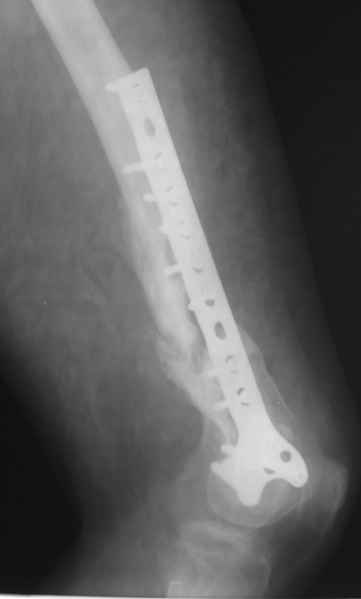

Обратился на консультацию больной. 24 декабря 2009г. попал в ДТП, получил переломы правого бедра, правой ключицы и  левой голени. 28 января 2010г. выполнен металлоостеосинтез правой бедренной кости пластиной. 8 апреля 2010г. выявлен неполный перелом пластины, на половину, по одному из отверстий для винтов. 15 апреля 2010г., на фоне сепсиса, выполнен реостеосинтез со свободной костной аутопластикой зоны перелома. Ранний послеоперационный период осложнился нагноением гематомы в месте операции. Последняя была эвакуирована с сохранением фиксатора. Рана зажила. Через два месяца открылся свищ с незначительным слизисто-гнойным отделяемым, функционирует до сих пор без изменений. При осмотре – в центре послеоперационного рубца свищ, около 2 мм в диаметре, со скудным отделяемым. Зонд, введенный в свищевой ход, доходит до металлоконструкции. Коленный сустав отечный, активные и пассивные движения в нем резко ограничены и составляют: сгибание – 100 градусов, разгибание – 160. Выполнили рентгенографию – ложный сустав, остеомиелит, пластина установлена слишком низко, «внутрисуставно», что вызывает постоянный синовиит и отек параартикулярных тканей.

Хотелось бы обсудить тактику дальнейшего лечения:

1.      Считаем, что у молодого человека, милиционера по профессии,  спасти коленный сустав другими способами, кроме БИОС, маловероятно.

2.      Чему отдать предпочтение – обычный вариант или ретроградный?